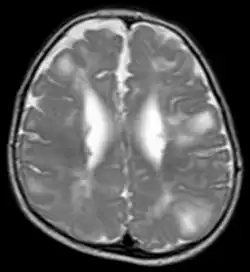

TSC in MRI

Classic intracranial manifestations of TSC include subependymal nodules and cortical/subcortical tubers.[6]

The tubers are typically triangular in configuration, with the apex pointed towards the ventricles, and are thought to represent foci of abnormal neuronal migration. The T2 signal abnormalities may subside in adulthood, but will still be visible on histopathological analysis. On magnetic resonance imaging (MRI), TSC patients can exhibit other signs consistent with abnormal neuron migration such as radial white matter tracts hyperintense on T2WI and heterotopic grey matter.

Subependymal nodules are composed of abnormal, swollen glial cells and bizarre multinucleated cells which are indeterminate for glial or neuronal origin. Interposed neural tissue is not present. These nodules have a tendency to calcify as the patient ages. A nodule that markedly enhances and enlarges over time should be considered suspicious for transformation into a subependymal giant cell astrocytoma, which typically develops in the region of the foramen of Monro, in which case it is at risk of developing an obstructive hydrocephalus.

A variable degree of ventricular enlargement is seen, either obstructive (e.g. by a subependymal nodule in the region of the foramen of Monro) or idiopathic in nature.